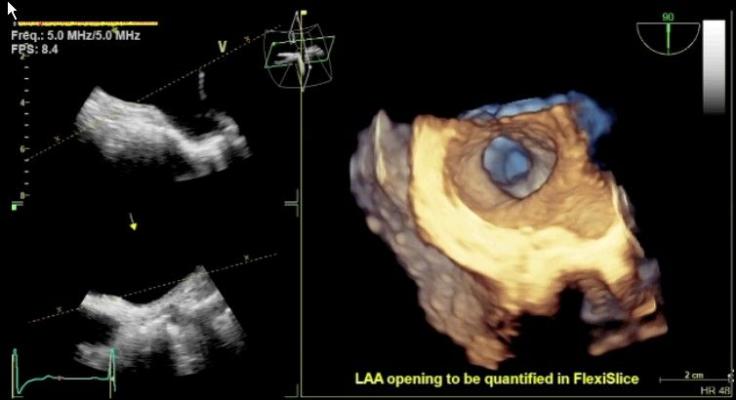

The value of TAVR depends on careful selection of patients who, while not surgical candidates, do not have such extreme comorbidities that overwhelm the benefits of TAVR and render the intervention futile. In selection of these patients, Doppler echocardiography has now replaced cardiac catheterization as the gold standard diagnostic technique for quantifying aortic stenosis (AS). A transthoracic echocardiogram (TTE) using an external probe on the patient’s chest can determine whether the AS is severe enough for TAVR. TEE supplements the information from TTE, providing precise measurements of the aortic valve annulus, critical for selecting the proper size of the implanted valve. Color Doppler TEE is used to determine the amount of regurgitation both pre- and post-procedurally and to check for paravalvular leaks. TEE is also widely used to guide device placement during the TAVR procedure.

GE Healthcare showcased its recently released Vivid E9 Breakthrough 2012 (BT12) cardiac ultrasound system, which includes a 3-D/4-D TEE probe. It offers tools to improve workflow efficiency through simplified image acquisition. It is designed for intuitive navigation and advanced, yet easy-to-use, quantification.

The new transesophageal probe allows 4-D dataset acquisitions to quickly visualize cardiac structures. It also can help quantify left ventricular pump function, myocardial deformation and mitral valve morphology.

The 4-D TEE probe includes triplane imaging, 4-D views and high frame rates. The system enables one-button acquisition of mitral valve images. In biplane mode, it has the ability to tilt and rotate at the same time, which aids in the accurate placement of devices such as the MitraClip. A new QuickRotate button provides consistency and accuracy by allowing users to rotate an image in 30-degree increments with a single click. The system also offers laser lines, a new tool to help understand the relationship between 2-D slices and 4-D views, helping visualize the linkage between 2-D and 4-D and improve depth perception.